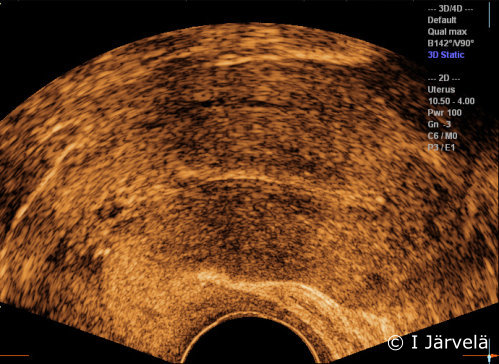

Situation one week later. The same pregnancy one week later. All the pregnancy material has drained off.

Pictures: Ilkka Järvelä; text: Dimitrios Scordas